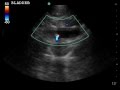

RSV Bronchiolitis Subpleural Consolidation on Mindray TE-X linear array transducer lung preset

6 m.o. Boy RR 40s, subcostal retractions with head bobbing, RSV pcr positive. Lung US using Mindray TE-X linear array transducer detects subpleural consolidation.

Images captured with Mindray TE-X, linear array transducer on lung preset.